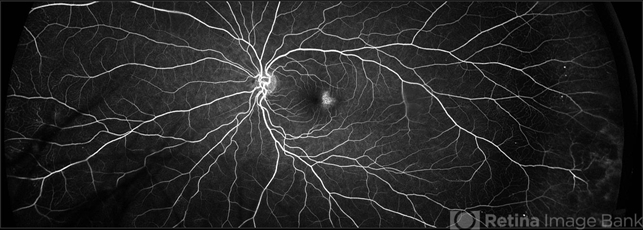

- macular telangiectasia type 2

- Imaging device

Scanning laser ophthalmoscope

Optos California - Description

- 45-year-old African American, female with type 2 diabetes mellitus, showing bilateral, temporal macular telangectasis and peripheral microaneurysms.